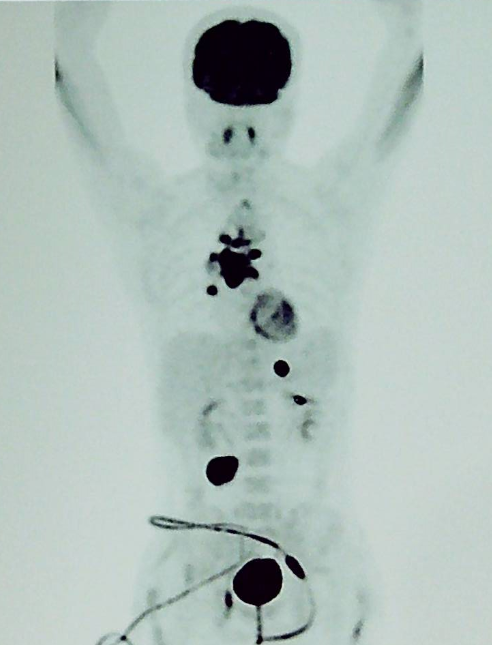

进一步完善 PET-CT:提示病灶累及胸椎、右上纵隔内、气管下段、左右主支气管周围、隆突下、右肺门多发淋巴结、胃小弯 (2.9 cm*2.6 cm)、右中下腹肠系膜多发淋巴结肿大伴代谢增高 (4.6 cm*3.7 cm);右侧闭孔内肌条等位置。临床分期 IVB 期。如下图 1: